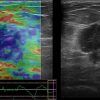

Ung thư vú

Ung thư vú - Ảnh 3

» Thông tin: Nữ giới – 51 tuổi.

» Lâm sàng: Khối tuyến vú.